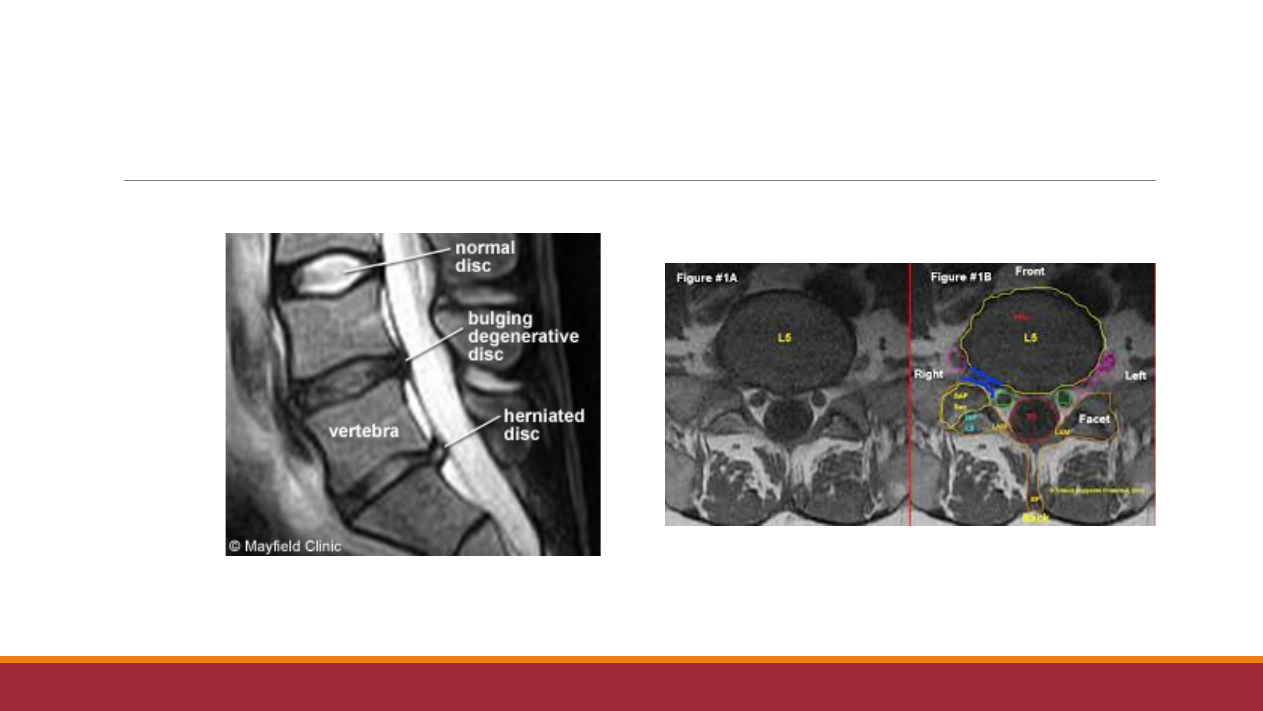

定

义

概

念

:

因

椎

间盘变性

,纤维环破

裂

,

髓

核突

出刺激

或

压

迫神

经

根

、

马

尾

神

所表

现

的

一种综合征

。

好

发

部

位

:腰

4/5

、腰

5/

骶

1

腰

解

剖

间盘结构